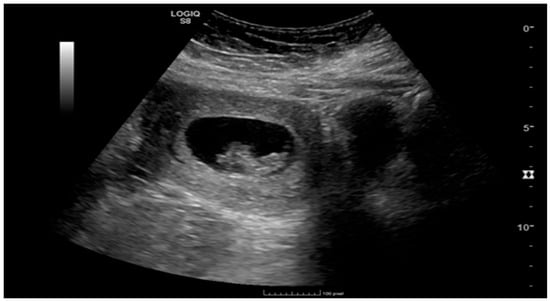

Ruptured Heterotopic Pregnancy: Laparoscopic Management, Preserving Intrauterine Viability

Pregnancy (HP), defined as the coexistence of intrauterine and ectopic gestations, is a rare condition, especially in spontaneous conception, but it is a life-threatening obstetric emergency when rupture occurs, with a reported maternal mortality rate of 0.03%. Diagnosis is often delayed because confirmation of an intrauterine pregnancy can mask clinical signs of a concurrent ectopic gestation. Early recognition and prompt surgical intervention are therefore critical to maternal safety and preservation of intrauterine viability. This case highlights the diagnostic challenges and successful management of a spontaneous ruptured heterotopic pregnancy. Case presentation: A 34-year-old Middle Eastern woman, gravida 4, with a spontaneous conception, presented with sudden severe lower abdominal pain and signs of acute hemoperitoneum (hypotension, tachycardia, and marked peritoneal signs). Transvaginal ultrasound demonstrated a viable intrauterine pregnancy at 9 weeks 4 days gestation, together with a ruptured left tubal ectopic pregnancy of similar gestational age. The patient underwent urgent laparoscopic left salpingectomy with evacuation of approximately 1200 mL of intraperitoneal blood and clots. Postoperatively, she developed significant anemia (hemoglobin drop from 11.2 g/dL on admission to 6.5 g/dL) requiring transfusion of four units of packed red blood cells. Serial ultrasonographic follow-up confirmed ongoing viability of the intrauterine pregnancy, which ultimately resulted in a live birth at term. Progressive resolution of the postoperative pelvic hematoma was also noted. Conclusions: Ruptured heterotopic pregnancy remains a diagnostic and therapeutic challenge. This case, along with a synthesis of the contemporary literature, demonstrates that a high clinical index of suspicion, timely ultrasound diagnosis, and immediate minimally invasive surgical management are paramount. Furthermore, rigorous postoperative monitoring and resuscitation, including targeted transfusion, are essential to achieve maternal stabilization while allowing continuation of a viable intrauterine pregnancy, with reported live birth rates exceeding 70% following timely intervention. Full article